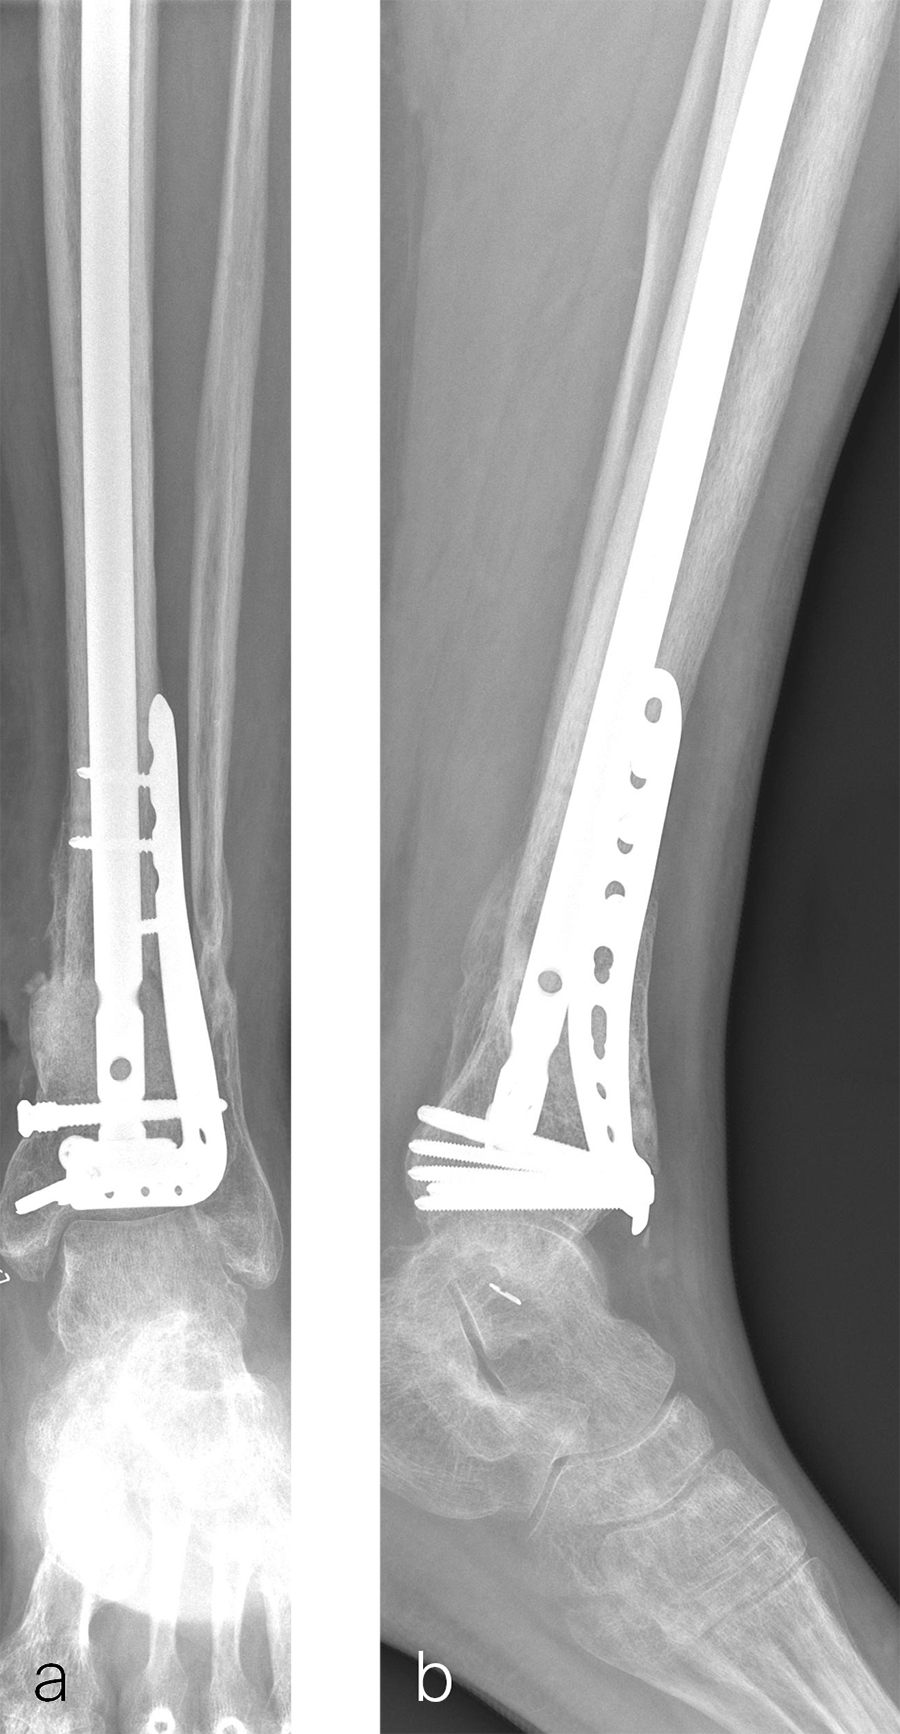

A 59-year-old man working for the city of Tulsa suffered an open distal tibia plafond fracture on the left leg when he fell into a sewer hole with raw sewage (Fig 1). The wound was grossly contaminated, and he was taken immediately to the operating room (OR) for incision and drainage and application of a spanning external fixator. Bone loss was noted anterior and medial (about 2.5 or 3 cm) but only about 2025% of the bone circumference.

After repeated incision and drainage, 2 days later the fracture was repaired with an anterior lateral tibial plafond plate (Fig 2). Vancomycin and tobramycin impregnated antibiotic beads were placed in the bone defect.

The patient was discharged on hospital day 6 to a rehabilitation facility with his left lower extremity in a splint and touch down weight bear allowance. He returned 2 weeks later with drainage from the medial traumatic wound. In addition, he had a gastrointestinal bleed from use of nonsteroidal antiinflammatory drugs. Once the gastrointestinal bleed was stabilized, he was taken the next day to the OR for another incision and drainage. Further, more significant, devitalized bone was resected, and an antibiotic cement spacer was placed (Fig 3). Deep culture samples were taken despite knowing the antibiotic resorbable beads had been placed in the wound at the time of initial closure. The plate was left in place, but a planned exchange plate/nailing was to be performed pending final culture results.

Cultures eventually yielded Klebsiella pneumoniae and Enterobacter cloacae. The patient was administered intravenous antibiotics for 6 weeks and was discharged home with therapy and nursing. He returned to the clinic with wound breakdown and an exposed cement spacer at 10 weeks after injury. Further bone debridement, spacer exchange, repeated culture samples, and plastic surgery were undertaken to help with wound coverage with a rotational flap. The microbiological culture was still positive for Klebsiella pneumoniae.

Two months later, the patient had a staged cement spacer removal and hardware removal followed by a new spacer placement (Fig 4). When microbiological cultures were negative for 5 days he was taken to the OR for definitive fixation and bone grafting. RIA bone graft from the ipsilateral femur was taken, a new anterior lateral plate was placed with an adjunct IM nail (and angle stable screws) as the distal plafond was now one articular block (Fig 5).

The patient has been followed up monthly for more than 5 months and has shown continued consolidation of the bone defect (Fig 6). Furthermore, he is weight bearing as tolerated without significant pain. The leg lengths are equal and the range of motion at the ankle is 10/25 dorsiflexion/plantarflexion. He has mild pain over the ankle joint but no pain at the fracture site.